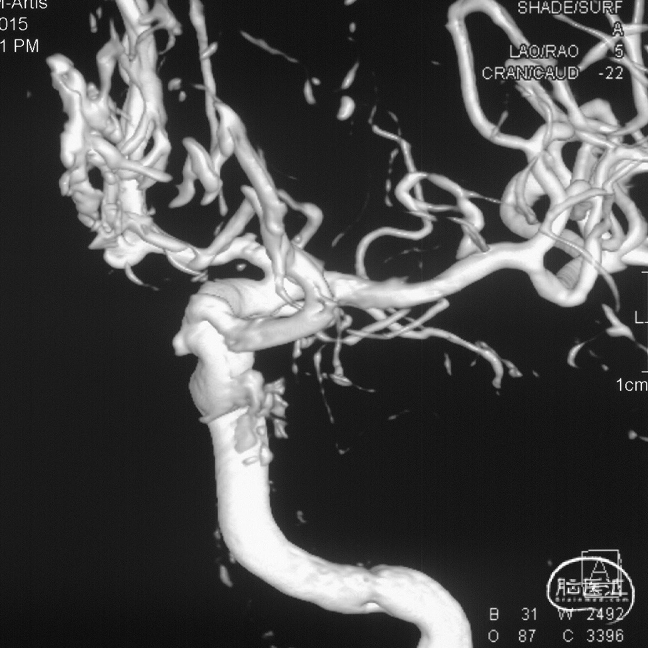

前颅窝底DAVF,由镰前动脉、双侧筛前、筛后动脉参与供血,通过皮层静脉向上矢状窦引流,引流静脉伴有瘤样扩张,Cognard IV型、Borden III型。由于脑膜中动脉-镰前动脉路径较为迂曲,超选困难,引流静脉迂曲扩张,预计到达瘘口起始端存在困难,决定经眼动脉-筛前动脉栓塞。

根据3D影像选择工作角度。

工作角度造影:黑色箭头为筛前动脉,白色箭头为筛后动脉,黄色箭头为镰前动脉,蓝色箭头为引流静脉起始部,红色箭头为视网膜中央动脉。拟通过眼动脉入路超选至筛前动脉进行栓塞。